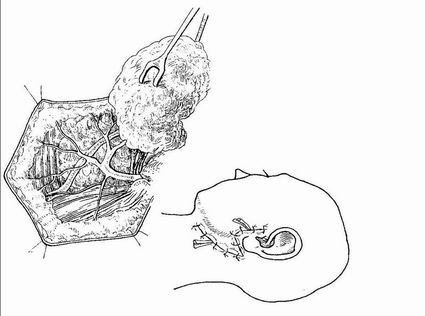

Chirurgie – GSM

Exstirpace

- Parciální výkony se neprovádějí

- Často jako součást bloku oblasti I

Prezervace ramus marginalis n. VII

Podvaz vasa facialia

Podvaz ductus Whartoni (přebíhá přes n. lingualis)